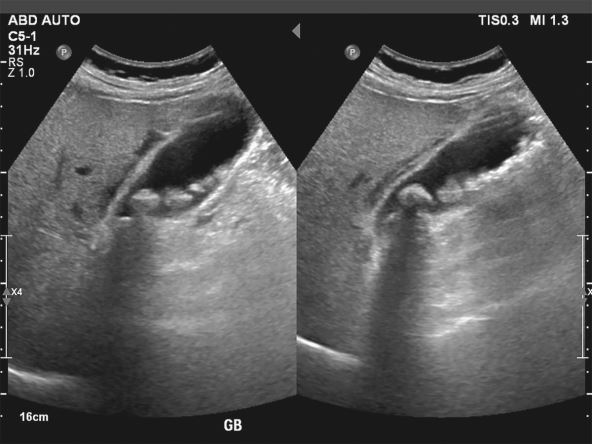

Dijagnoza žučnih kamenaca je sada brza i bezbolna, a zlatni standard je abdominalni ultrazvuk. Ova metoda sa velikom tačnošću otkriva prisustvo kamenaca, njihovu veličinu i moguće znake upale žučne kese.